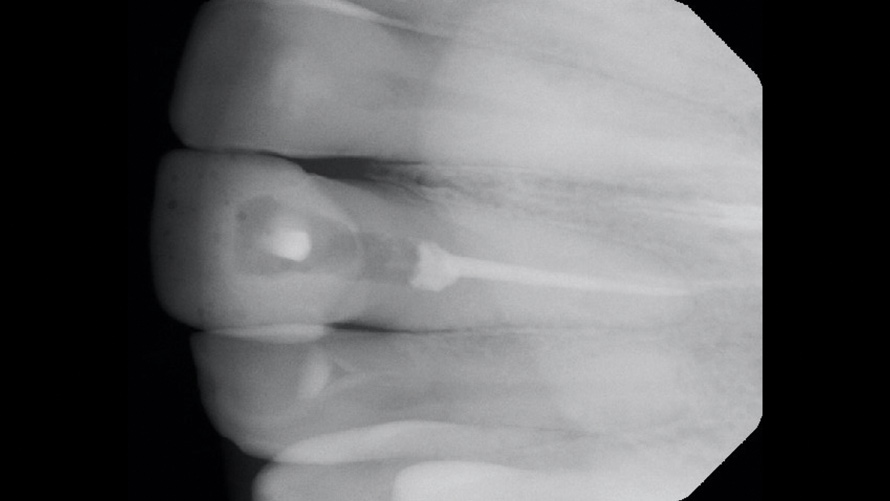

(4.) Case 2: Preoperative radiograph of the maxillary left central incisor, demonstrating existing nonsurgical root canal therapy.

Figure 4

In the second case, a preoperative periapical radiographic examination revealed that the patient had previously undergone nonsurgical root canal therapy and that the existing root-filling material stopped 3 mm to 4 mm short of the apex (Figure 4). Further examination revealed an intact lamina dura and normal bone trabeculation. Under high-power microscope magnification, the existing root canal sealer appeared to be the cause of the intrinsic staining; therefore, it was deemed necessary to re-treat and refill the existing root canal.